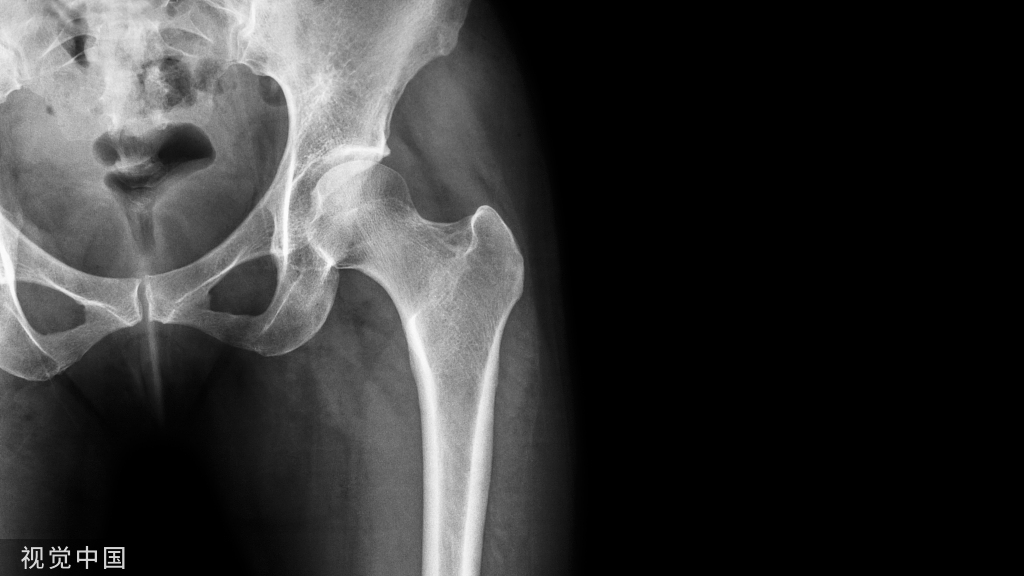

病例一

42岁女性,间歇性发热11个月,持续不断的腰痛7个月,双下肢无力1个月入院。体格检查发现L3、L4棘突附近压痛,无放射性疼痛。直腿抬高试验,右腿70,左腿90,双下肢肌肉萎缩。实验室检测WBC 6.61×109L,布鲁氏菌抗体滴度为1:16。影像学表现见下图a~f

图a、b、c、d  CT扫描 显示L4椎体终板多处不规则骨破坏,伴有边缘硬化,无死骨。骨破坏区周围呈花边样骨赘增生,椎体周围软组织肿胀。

图e、 f  MRI成像显示L3和L4椎体长T1和长T2斑块信号,边界不清。L3/L4椎间隙变窄,伴有椎旁软组织肿胀和硬膜囊轻微受压。